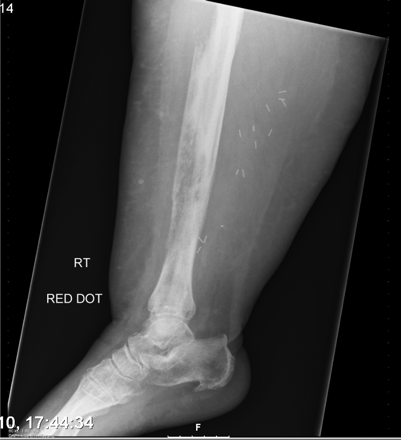

X线片表现:好发于肋骨、脊柱、骨盆及颅骨,其次为肱骨、股骨,也有转移至胫、腓、尺、桡及足骨者;破坏灶单发或多发,大多为溶骨性破坏,边缘模糊,骨皮质常有破坏,有时肋骨、坐骨及长骨受累,骨干可完全被破坏吸收而不留痕迹;肺癌成骨性转移很少见,表现为斑点状或絮状密度增高影,密度由毛玻璃状高至象牙质样。部分病例出现软组织肿块,一般无骨膜反应。

非小细胞肺癌骨转移

肺癌转移

1.周围型转移:发生于手足短骨的转移,有文献报道163 例手骨转移68例原发瘤在肺部,占41.7%,表现为末节指、趾骨溶骨性破坏,伴有球形或分叶状软组织肿胀;

2. 骨皮质转移:易侵蚀骨皮质,形成斑片状、碟形或地图样骨缺损,以肱骨、股骨近端多见,也见于胫骨、尺桡骨。